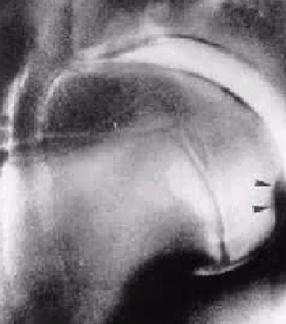

Examen endoscopic al laringelui – vezi foto.

Imaginea nu este clara !!!

Cerinte suplimentare

• este modificata pozitia epiglotei, se observa aderenta epiglotei la cartilajele aritenoide – daca da, atunci este vorba despre aderentele epiglotei

• cum a aparut simptomatologia – s-a accentuat în timp pe parcursul a câtorva saptamâni sau luni sau într-un interval mai scurt?

• palparea laringelui imediat dupa efort accentueaza cornajul? – daca da, atunci este vorba de o hemiplegie sau pareza laringiana

• ce releva examenul endoscopic – apare un asincronism al miscarilor proceselor corniculare în timpul respiratiei? – daca da atunci este vorba de hemiplegie laringiana – sau daca este vorba de absenta miscarilor - pareza laringiana (asta daca apar crize asfixice frecvente si dispneea este permanenta)

Diagnostic

• aderentele epiglotei

• hemiplegia laringelui

Examinarea endoscopica releva în majoritatea cazurilor un asincronism al miscarii proceselor corniculate în timpul respiratiei – vezi foto

Diagnostic – hemiplegia laringelui – este afectata partea stânga